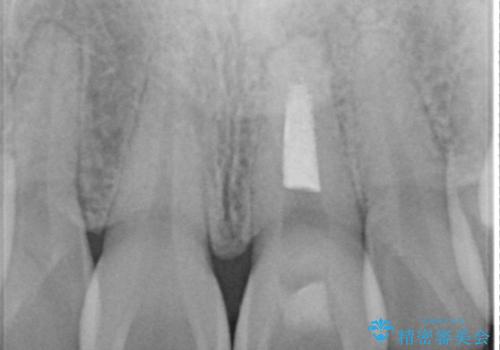

- 前歯が、ポロポロ欠けてくることを主訴で来院された女性です。

以前に根の治療しましたが、最近になって色なども気になり来院されました。

神経の治療をしている歯は、時間と共に色がどんどん変色していきます。

また、神経、血液供給がなくなってしまう影響から歯も脆くなっていってしまうため、歯が割れてしまうリスクもあります。